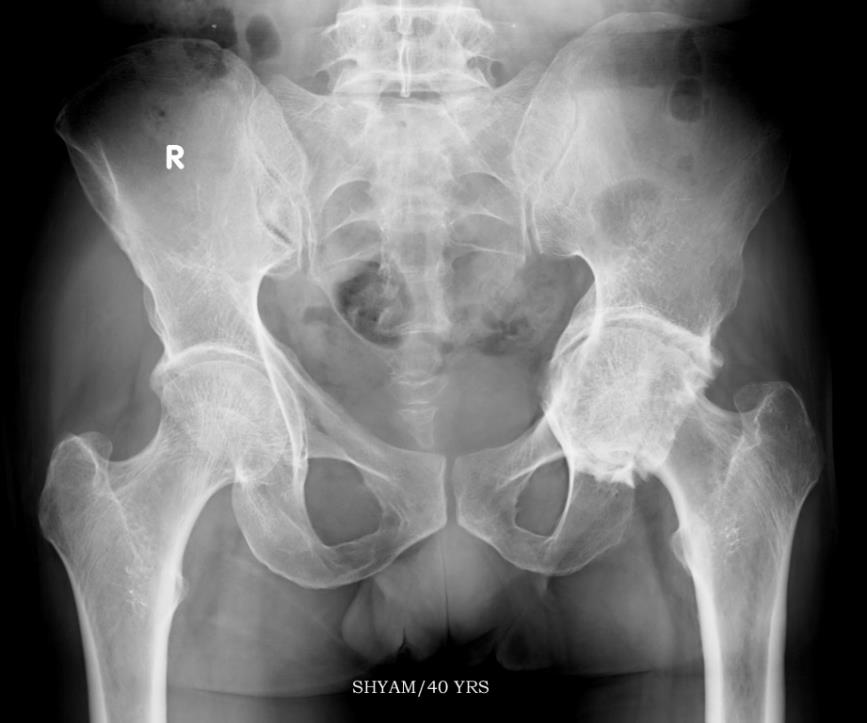

Bilateral protrusio with negative sloped sourcils and medial osteoarthritis on the left side

Bilateral protrusio with negative sloped sourcils and medial osteoarthritis on the left side.